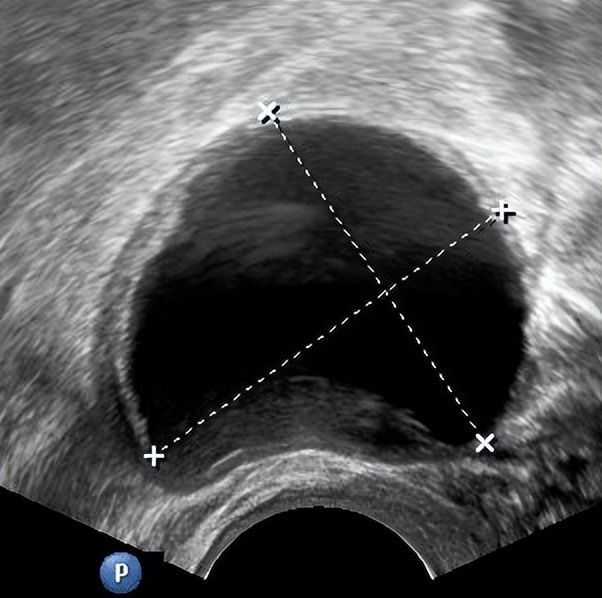

02、 黄体囊肿

卵泡正常排出卵子后,会演变为黄体,正常直径为2~3cm,若黄体内毛细血管出血或液体积聚,则形成黄体囊肿。

黄体囊肿多发生于月经周期的后段(第14~28天),由于这种囊肿会持续分泌孕激素,可能导致月经推迟。一般来说黄体囊肿会自行消退。但极少数会发生破裂,引发下腹疼痛和盆腔内出血,此时需要及时就医,根据严重程度来决定保守治疗或手术治疗。